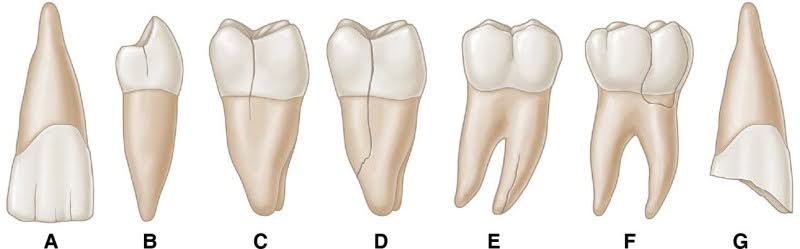

2. Cracked Tooth

A cracked tooth can be difficult to detect but is a frequent cause of pain when chewing. The crack may not be visible, yet it can allow pressure to affect the inner structures of the tooth.

A cracked tooth can cause pain only when biting—especially when releasing pressure.

Signs:

- Pain when chewing, but not constant

- Sensitivity to hot/cold

- No obvious visible damage

Treatment:

- Dental crown

- Root canal (if nerve affected)